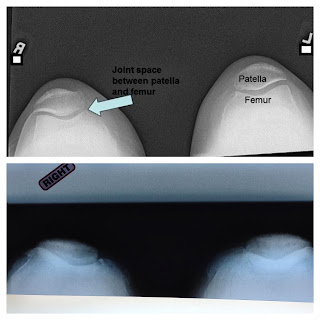

The top image is of a normal set of knees. The bottom one is

of Dad’s knees that are soon to be replaced with bionic ones. Meanwhile, he